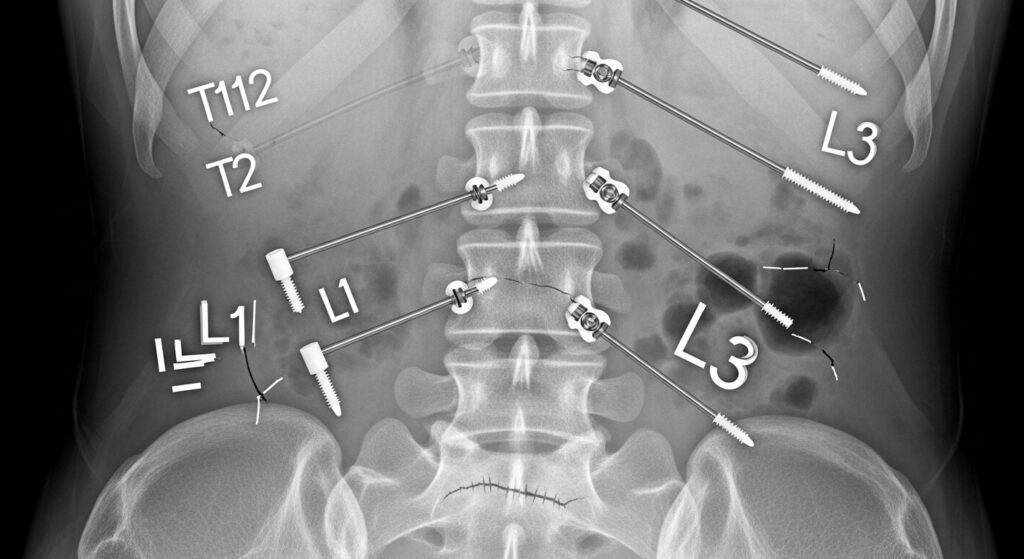

En casos graves, cuando los tratamientos conservadores no han funcionado, la cirugía puede ser necesaria. La cirugía puede implicar la eliminación de discos herniados, la fusión de vértebras o la instalación de un dispositivo de fijación para estabilizar la columna.